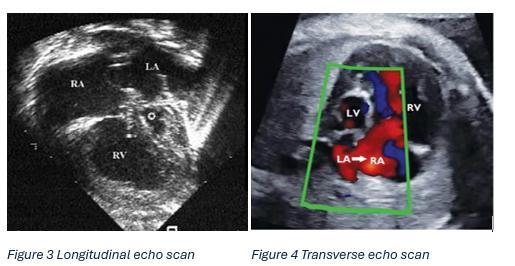

Hypoplastic Left Heart Syndrome

Hermione Kerr Y12 Page 67